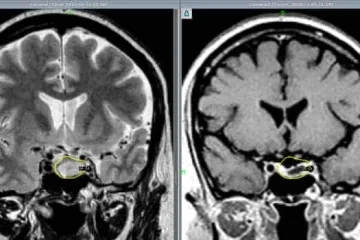

Армянские врачи удалили редко встречающиеся 3-килограммовые метастатические опух...